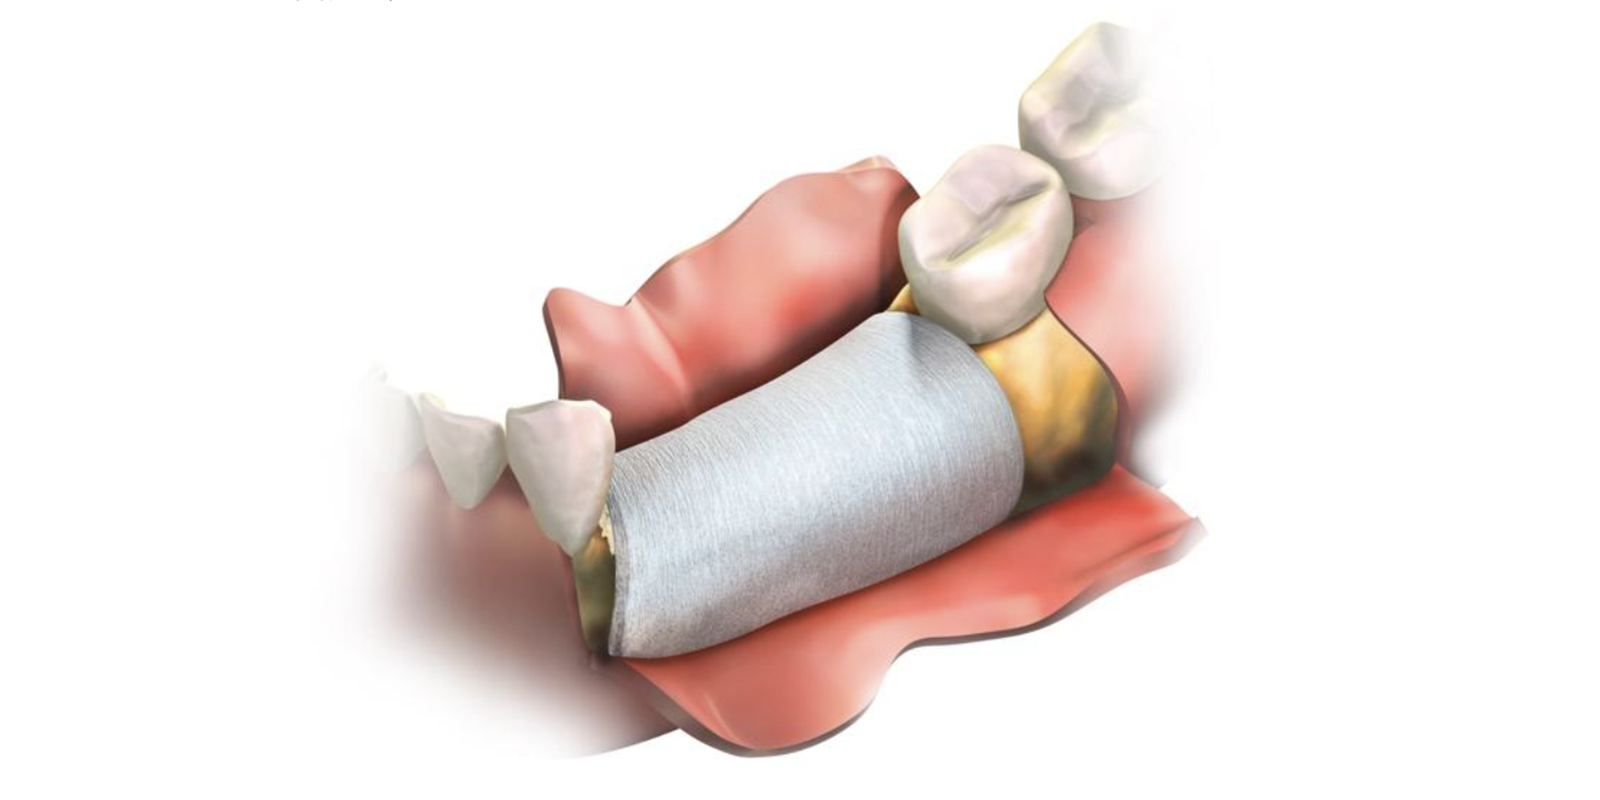

結合組織移植手術について

主に上顎の奥歯の内側から歯ぐきを採取して、歯ぐきが下がっている部分の上皮と骨膜との間に移植する手術です。

現在インプラント治療にも応用されています。

移植する範囲が大きい場合は、やけど治療の際などに使用する皮膚の移植材(無細胞性皮膚基質)を用いて移植する方法もあります。

歯周組織誘導法(GTR)

歯周組織誘導法(GTR)とは

歯周病で失われた骨の部位に、膜を張ることによって、上皮の侵入を防ぐことが出来、歯周組織が修復するためのスペースを確保する方法です。

歯周組織誘導法の期待される効果

歯を支える土台となる歯周組織の再生を促し、見た目の改善だけでなく、インプラント治療に必要な骨の厚みを作れる可能性が高くなります。

歯周組織誘導法の治療の流れ

- 麻酔をして、治療する部分の歯ぐきを

切開します。 - 目視下で確認していき、プラークや歯石、歯周病に侵された歯ぐきと歯槽骨の表面を取り除きます。

- 歯槽骨や歯根膜が不足している部分を、人工膜(メンブレン)で覆います。

- 縫合し、歯周組織の再生まで一定期間置きます。(期間には個人差があります)